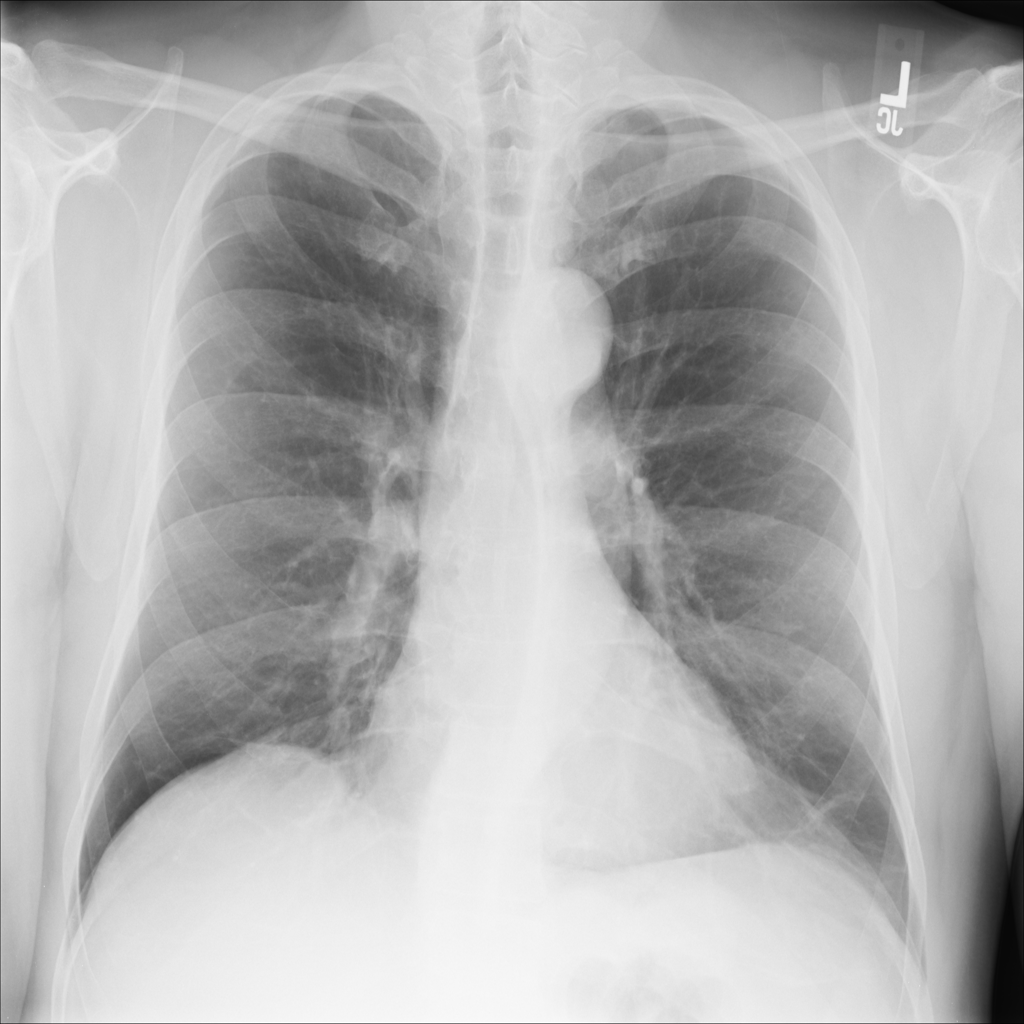

PAT-0E82 · IMG-000Emphysema

PAT-0E82 · IMG-000

AP